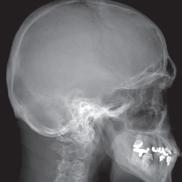

“When using standard MRI approaches, we are limited to brighter and darker shades of gray,” says MIITT co-director, Nicole Seiberlich, PhD, Research Professor of Cardiovascular Imaging and Associate Professor of Radiology. While radiologists are both skilled and experienced at reading and interpreting these images, introduction of a numerical measurement technique eliminates subjectivity, providing readers with specific data. “With our proprietary method, Magnetic Resonance Fingerprinting (MRF), radiologists can acquire quantitative data on multiple important properties simultaneously, which improves the accuracy of the diagnostic information. These quantitative tissue property maps include actual numbers that give experts reproducible and actionable results. It has been evaluated in brain, prostate, liver, cardiac, and musculoskeletal imaging.”